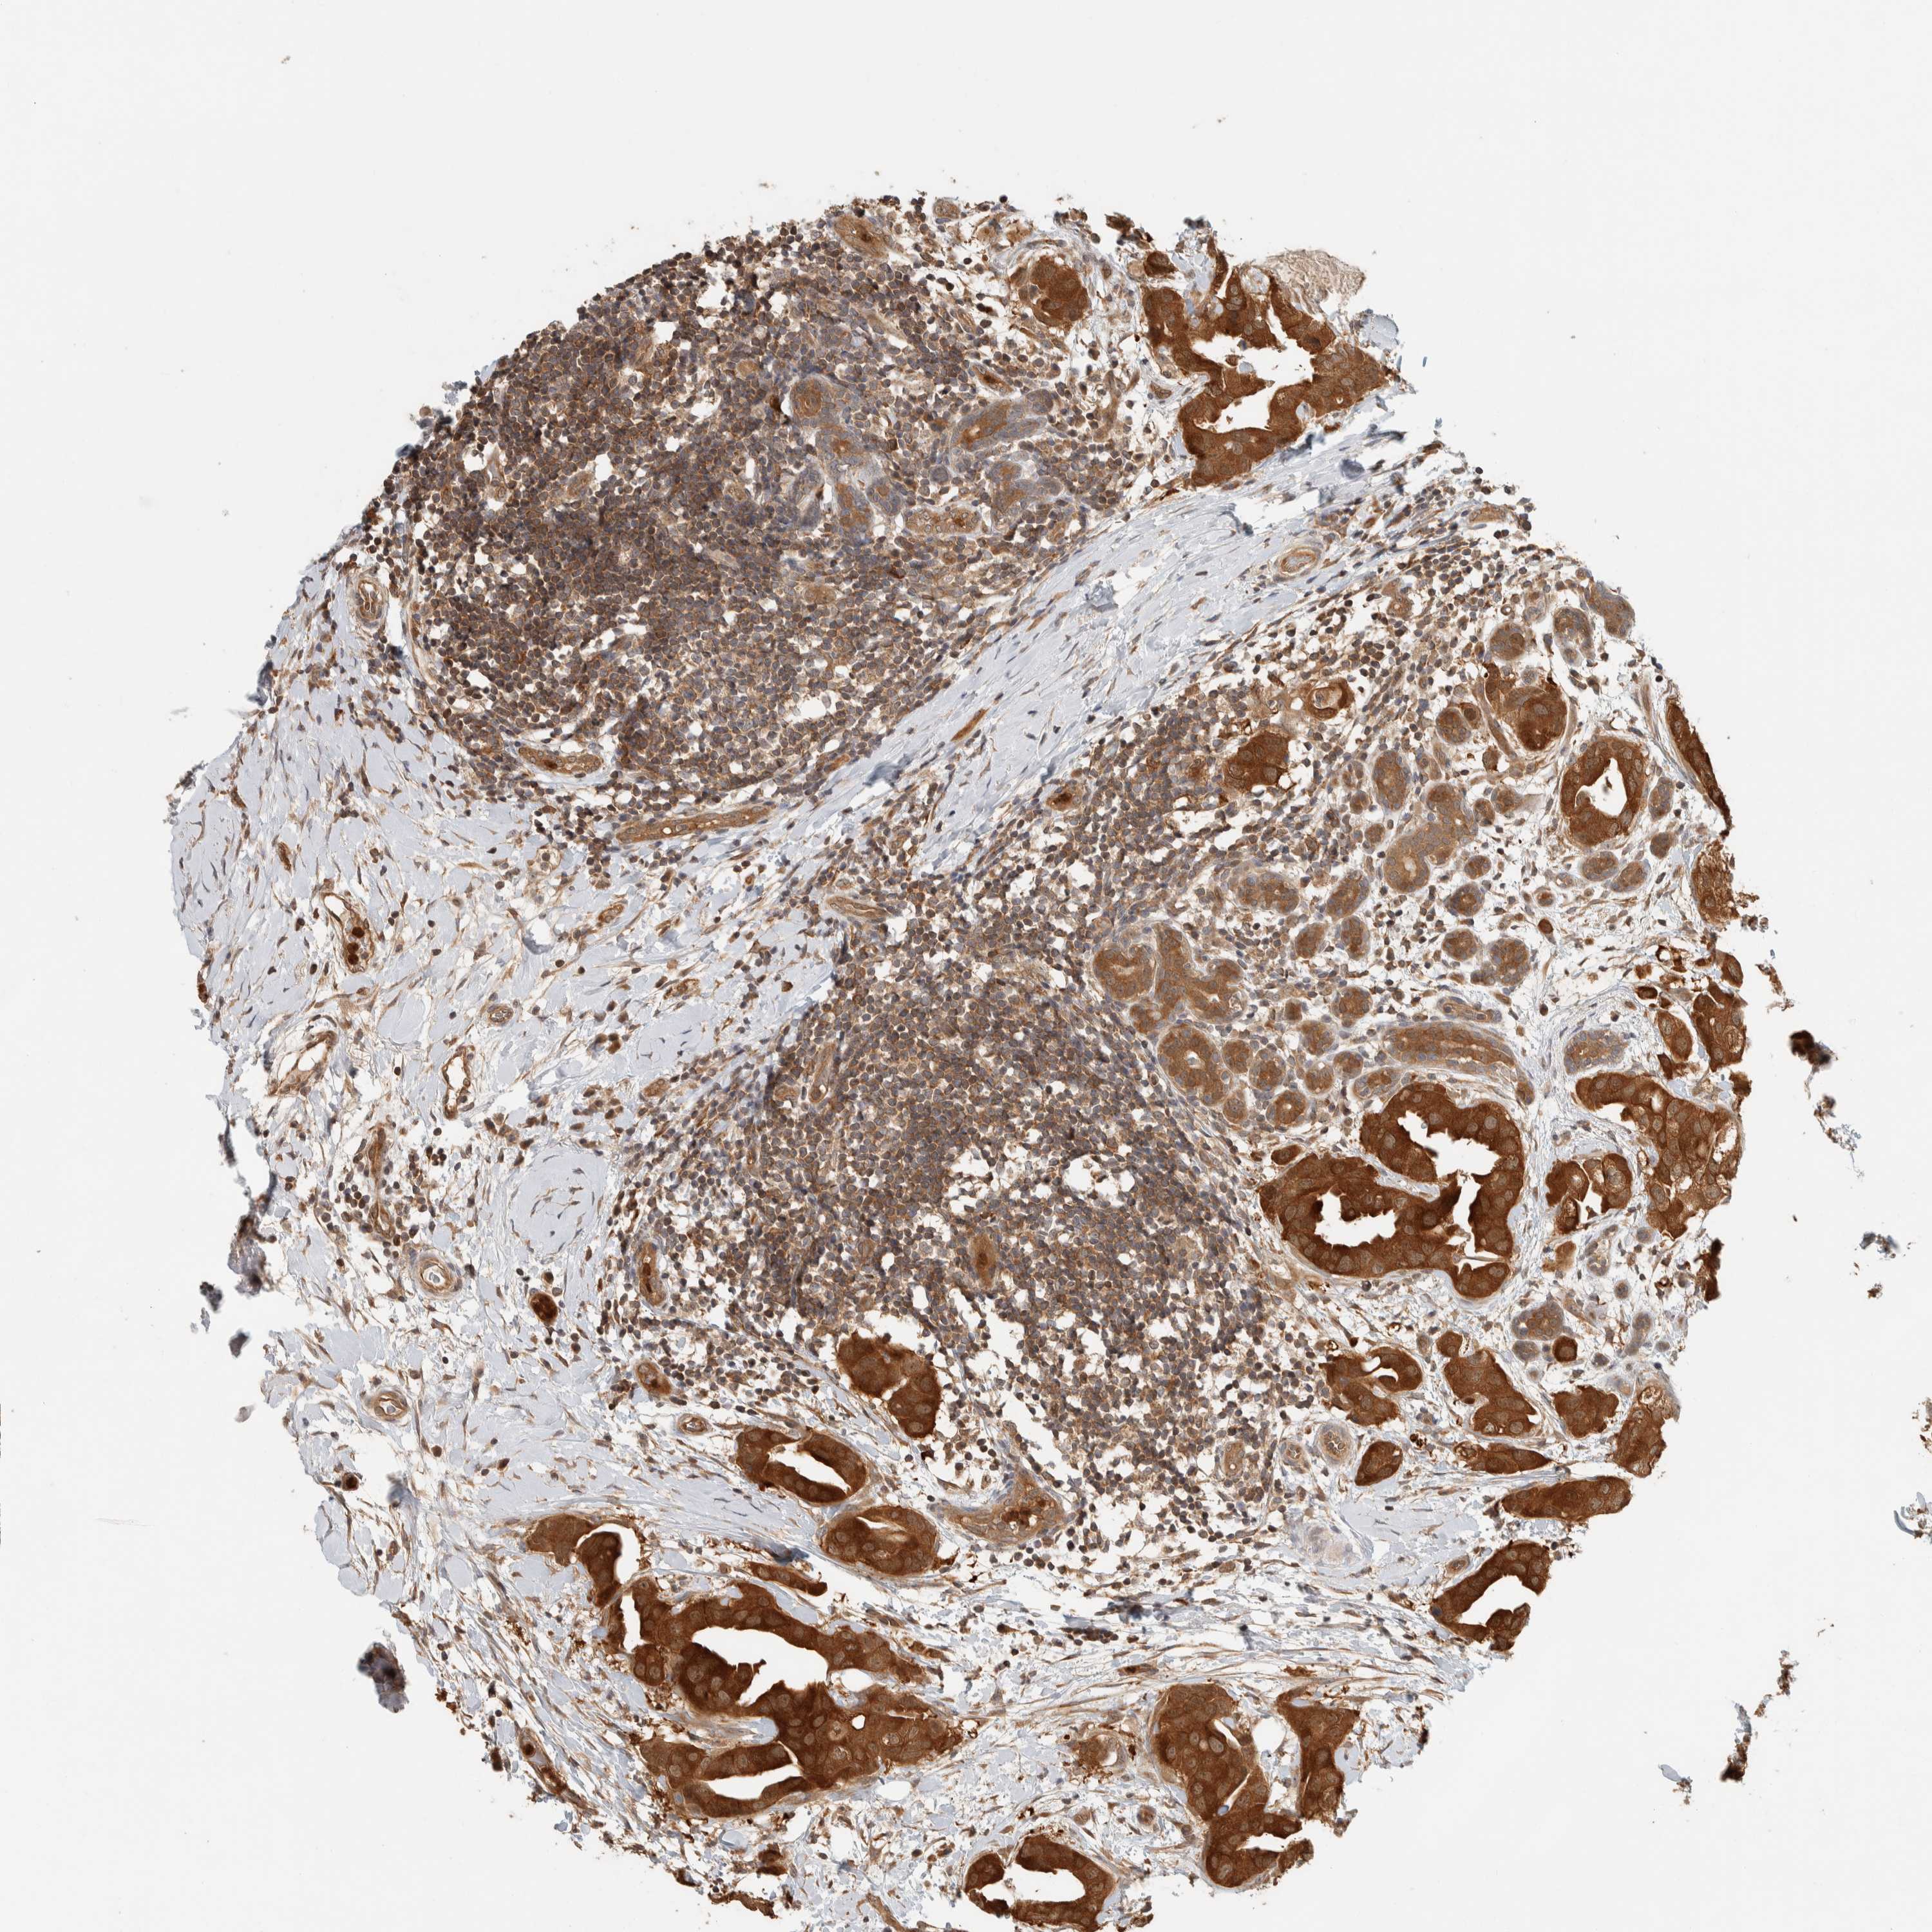

BRCA TCGA BRCA VALIDATION PROTEIN EXPRESSION